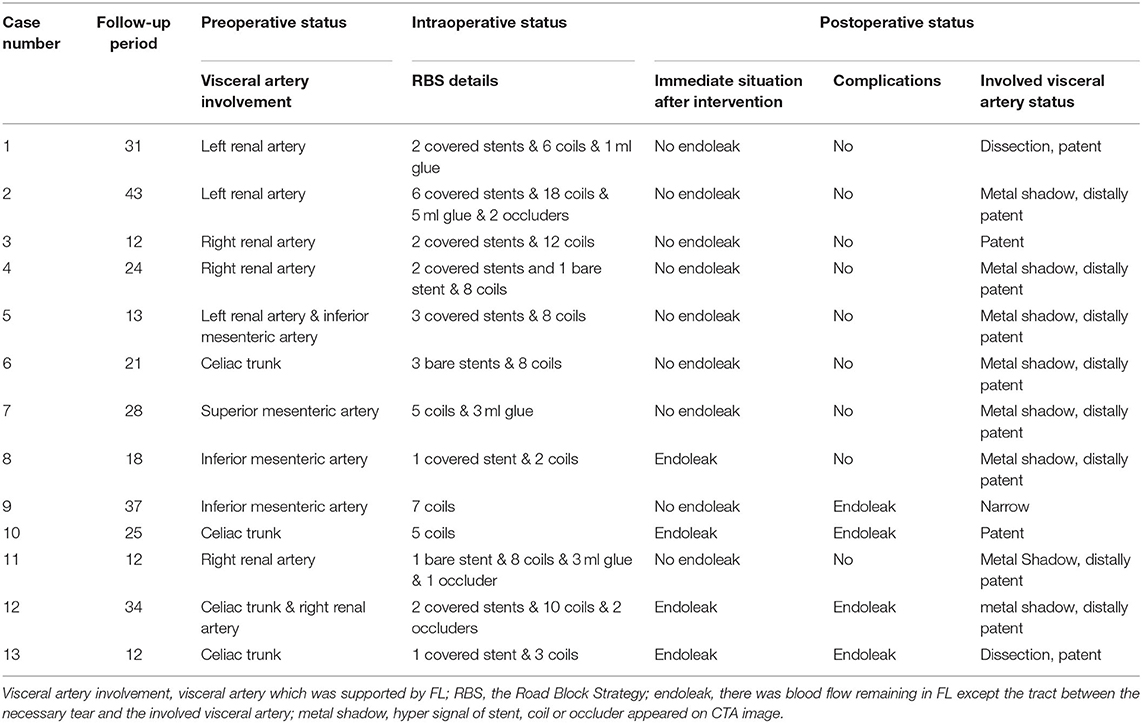

Details of the two-step procedure for RBS are presented in Table 2. The treatments of non-RBS patients are not listed in Table 2 for their visceral region were not treated additionally and all of their treatments have been listed in Table 1. At least one visceral artery (celiac trunk, superior mesenteric artery, inferior mesenteric artery, or renal arteries) was supplied by the FL in all RBS or non-RBS patients. During the first step of RBS, covered stents were used in 8 patients (62%), bare stents in 3 patients (23%), and no stents were used to maintain visceral artery perfusion in the remaining 3 patients with only the initial tear preserved.

For the second step of RBS, 7.7 ± 4.1 (range 2–18) coils were used in each patient. Coils were placed in the true lumen in 5 patients (38%) and the visceral artery in 3 patients (23%) during embolization, and successfully repositioning was observed in all cases. The coils were extended to the rest of the FL; care was taken to avoid excluding visceral arteries. A total of 4 patients (30%) underwent Onyx glue injection (mean volume of glue injected was 0.9 ± 1.7 ml), and 3 patients (23%) underwent occluder placement due to a large FL (minimum FL diameter > 20 mm) (Figure 4). Intraoperative angiography can be seen as Figure 4.

The average follow-up period in RBS patients is 23.85 ± 10.38 months, while that is 26.46 ± 15.55 months in non-RBS patients. Segmental complete thrombosis in the FL was found in 9 patients immediately after RBS, while segmental complete thrombosis formed in 2 patients in non-RBS group and caused one case of left kidney atrophy. Although endoleaks were observed in 2 patients immediately after RBS, blood flow in the FL was limited. Overall, the only complication was endoleak (n = 4), and no patient experienced acute sympoms in the follow-up period. As for non-RBS patients, complications include 1 case of aortic rupture, 2 cases of denovo aortic dissection, 1 case of enlargement of aortic dissection involvement, 1 case of left kidney atrophy, and 9 cases of continuous enlargement of aortic lumen. As for RBS patients, no cerebral infarctions, new dissections, and visceral artery stenosis or occlusion were observed during the follow-up.

After RBS, 9 patients experienced abdominal segmental complete thrombosis. Comparison of the preoperative and the latest postoperative data showed significant differences in three indicators of aortic remodeling at the max diameter level of the total aorta. The maximum TL diameter was significantly increased (14.57 to 18.34 mm, p ≤ 0.033), while decreases in blood flow area in the FL (1042.59–to 158.76 m2, p < 0.001) and Rbf (ratio of blood flow area in FL to FL area) (80–18%, p = 0.002) (Table 3), were observed. In terms of outcomes of involved visceral arteries, all patients exhibited patent visceral arteries. A total of 12 patients experienced good visceral artery blood perfusion, and 1 patient exhibited mild visceral artery stenosis related to congenital renal artery malformation.